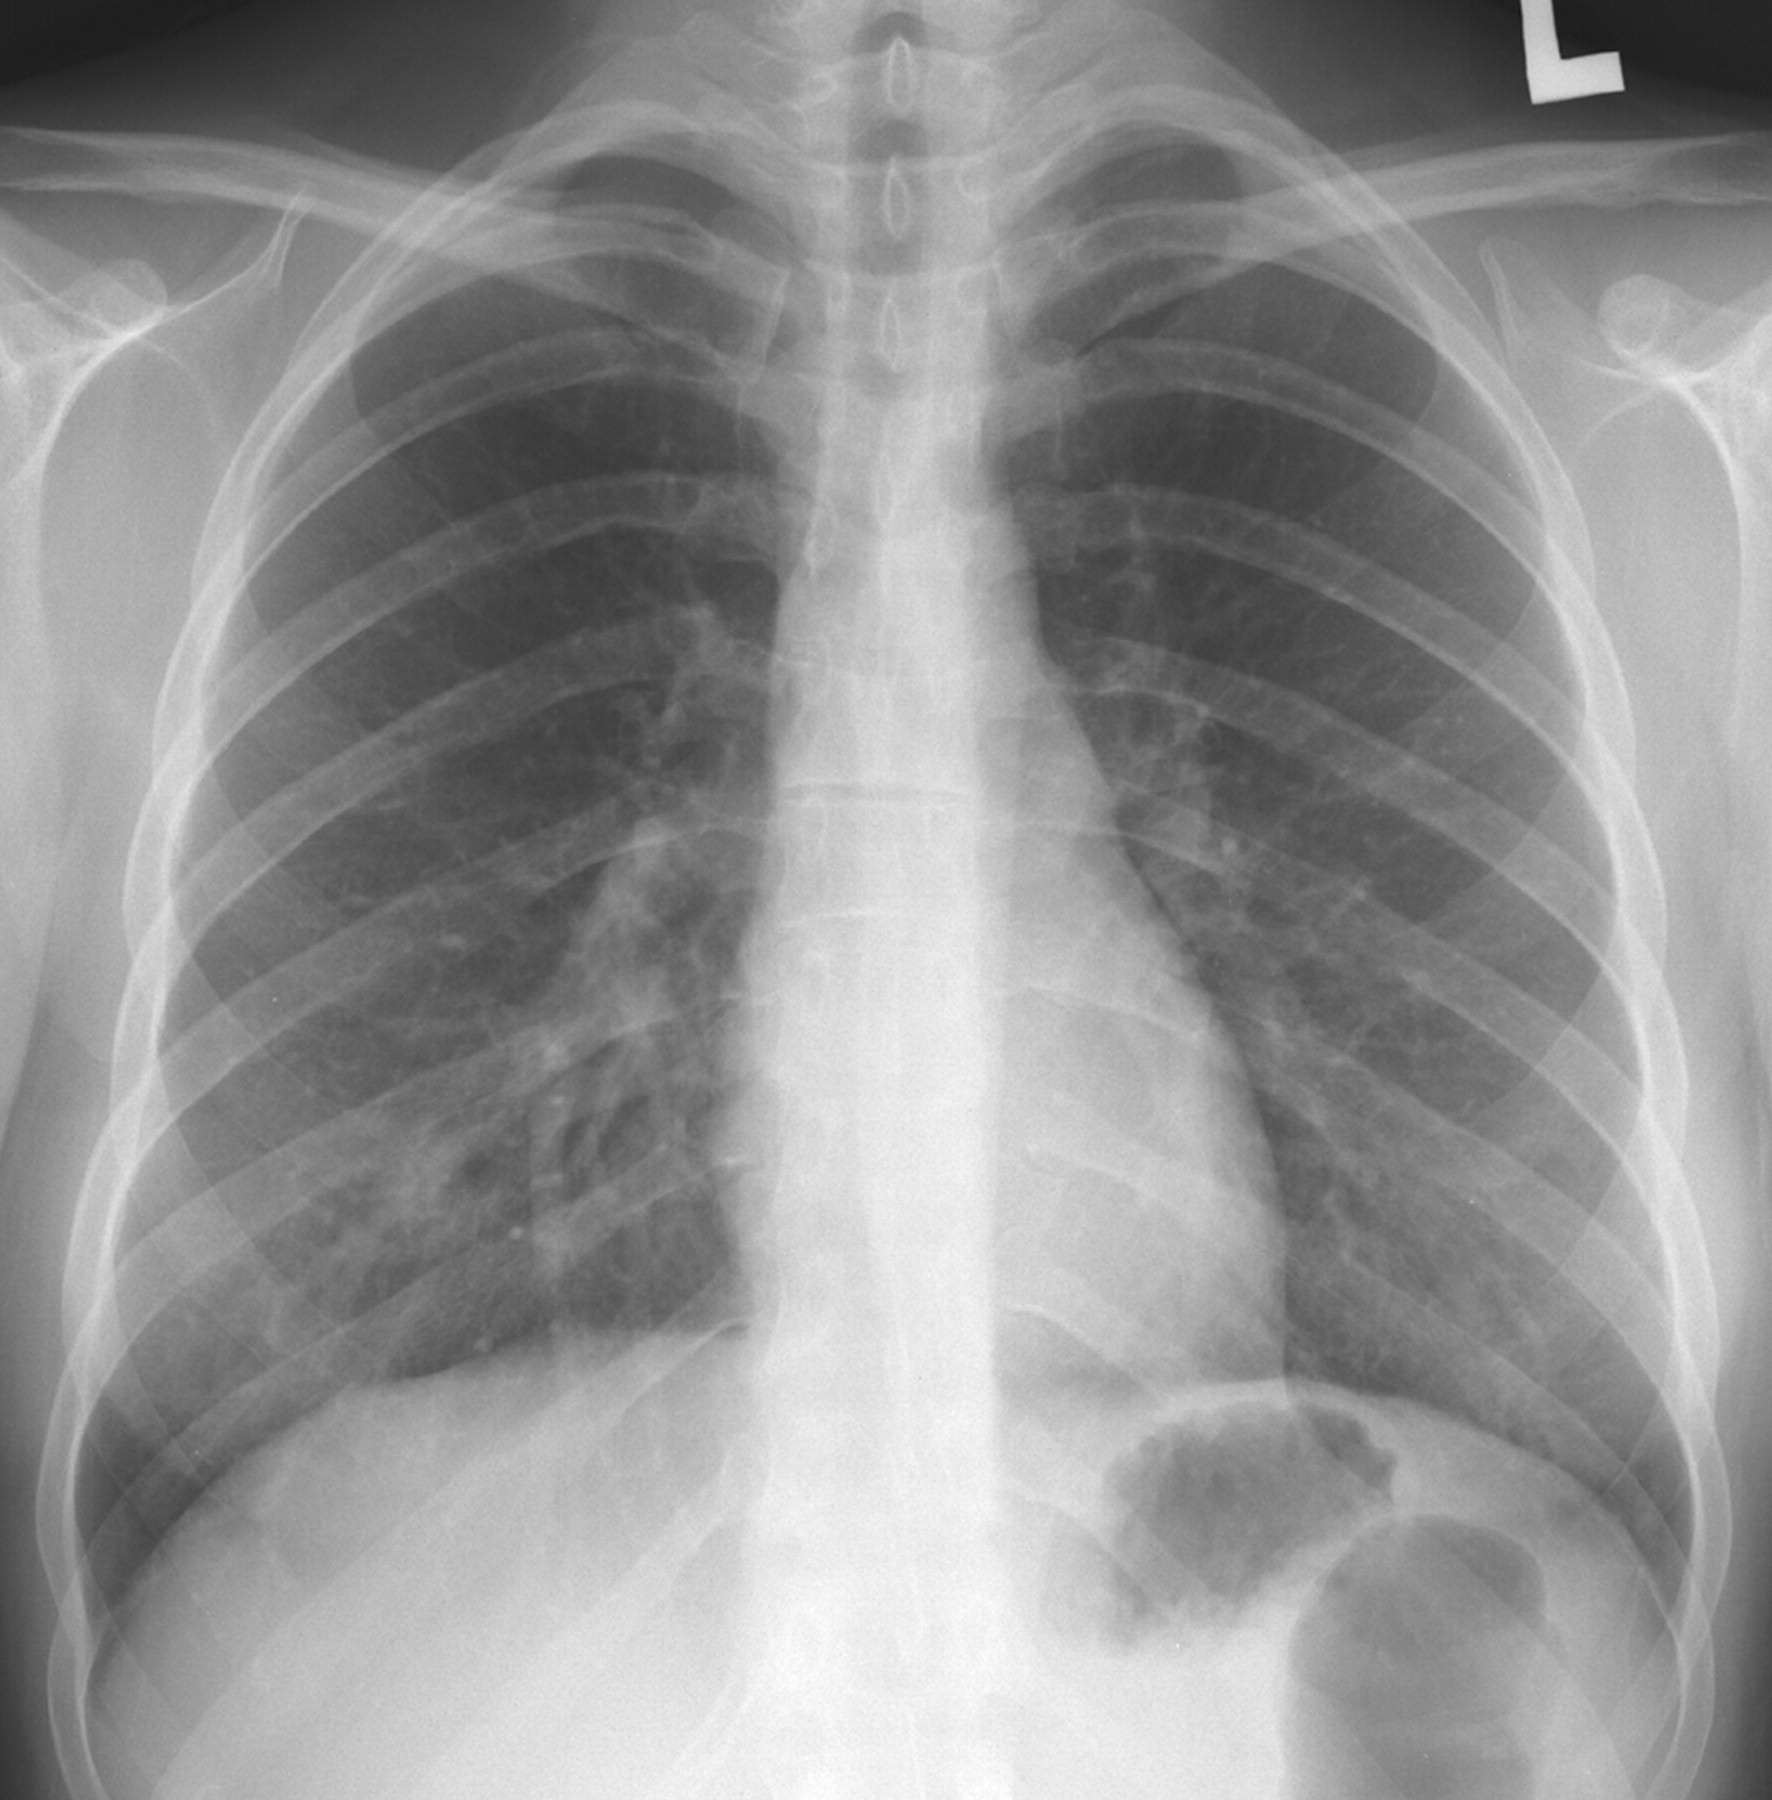

Two datasets DS1 and DS2 were constructed using extracted data from the above two data repositories for training and testing proposed model and other pre-trained models. DS1 includes about 150 CXR of Covid-19 and 150 CXR of normal subjects which was designed for binary classification problem. DS2 was designed for three class classification where we differentiate Covid-19 infected subjects from normal and other pneumonia type infections. This dataset consists of 150 Covid-19, 150 other pneumonia and another 150 instances for normal CXR images. Within the samples of other pneumonia CXR, there are cases of bacterial infections, fungal infections and other viral infections of subjects. Figure 1 presents representative CXR images for Covid-19, bacterial, fungal, other viral and normal patients respectively.

\zihao-5Fig. 1: \zihao-5Representative CXR images from datasets corresponding to different infections

In these sample CXR images, there are certain areas with hazy opacification or increased attenuating as these areas are filled with some substances other than air. This is an indication of displacement of air by fluid and a collapse of periphery of lungs due to various infections. Though these areas are visible as more grey and cloudy compared to darker areas with lower attenuation, differentiating the cause of infection is not possible for human eye alone. Further, the specific radiographic patterns can be variable depending on different viral strains making it hard even for expert to diagnose using CXR alone. This further implies the demand for efficient and accurate automated CXR based techniques for disease diagnosis.